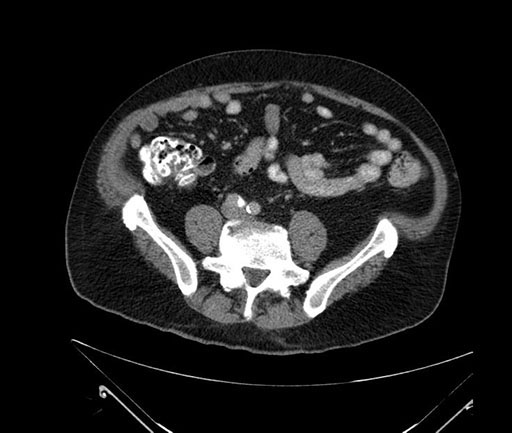

Whipple (pancreaticoduodenectomy) [case 7]

Axial - 3 months prior